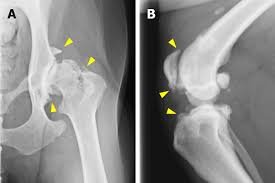

hip dysplasia dr hart

• hip dysplasia

hip arthritis dog

Hips

Hip arthritis is very common in older dogs and may cause trouble rising, stiffness, or a swaying rear gait.